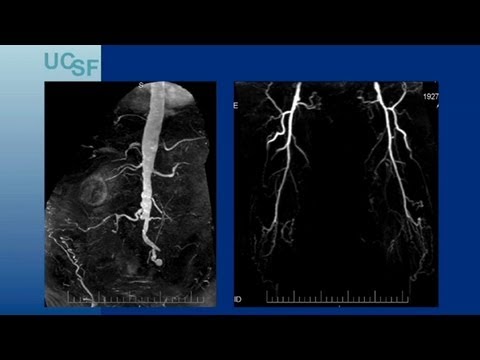

Endovascular Approaches for TASC C/D Aorto-iliac Lesions - UCSF Vascular Surgery Symposium 2013